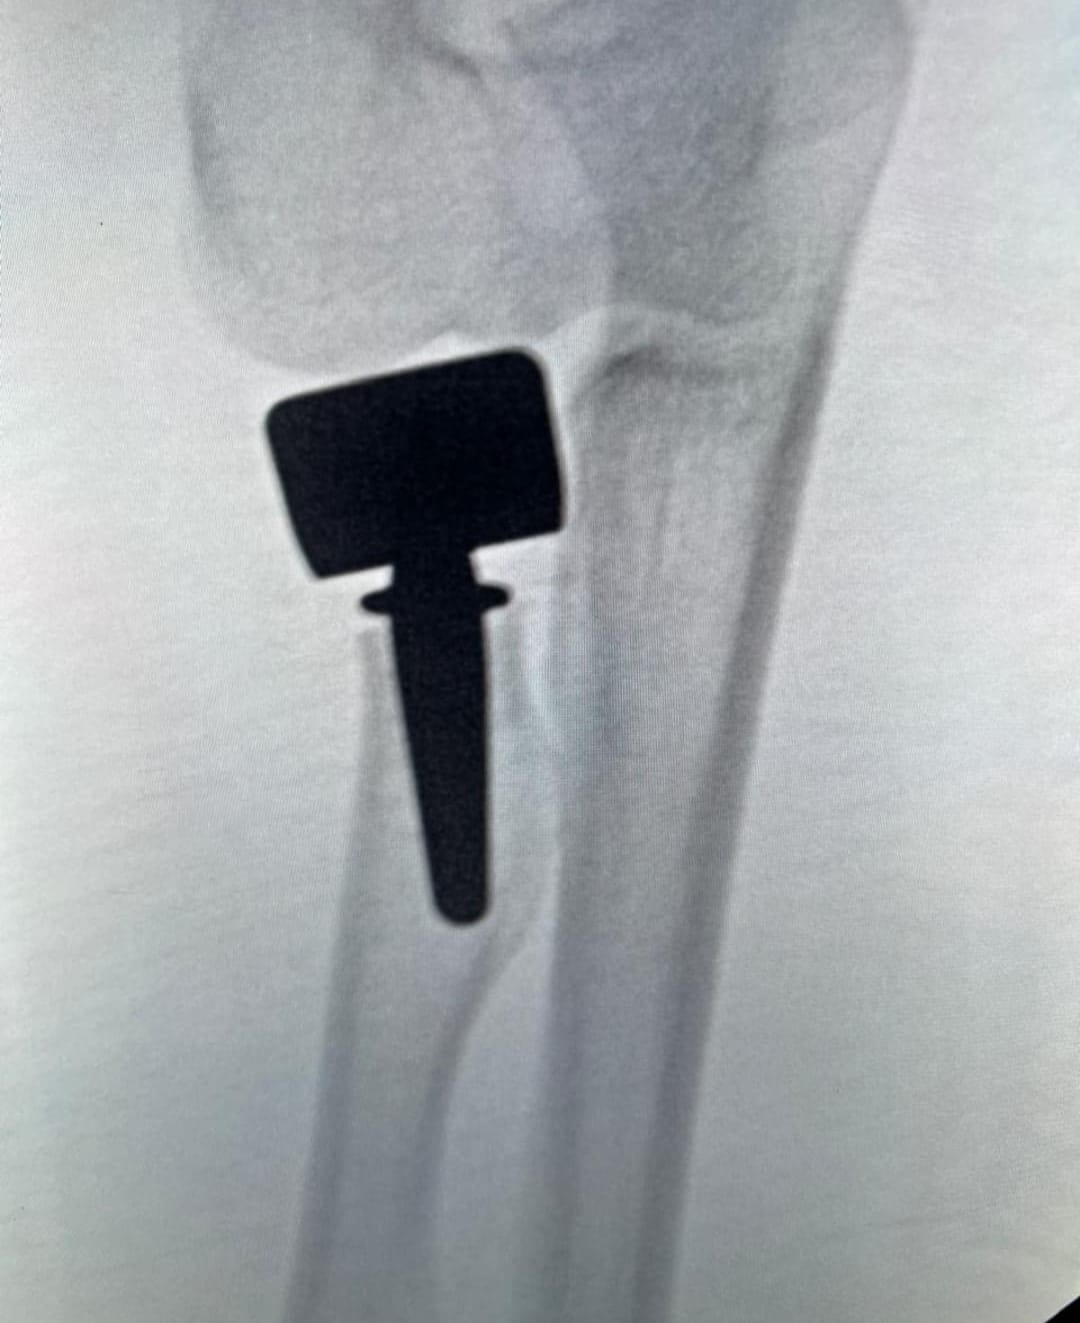

CASOS